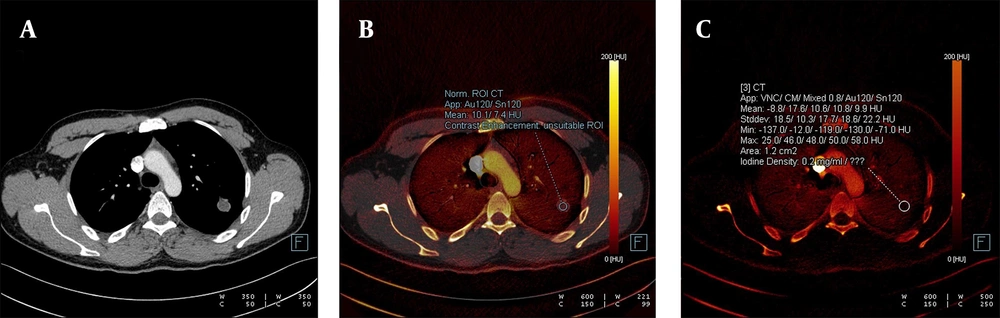

A, The weighted average image; B, The virtual iodine-enhanced dual image; and C, The image of the iodine load are shown in dual-energy computed tomography, DECT. A solitary pulmonary nodule with an infinitesimal contrast load and an iodine load of 0.2 mg/dL was observed. The diagnosis was confirmed as a hydatid cyst through histopathological examination.